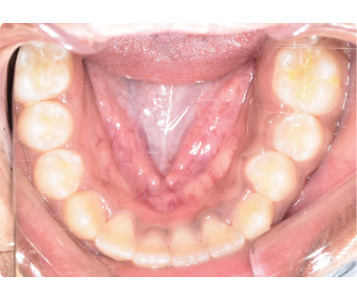

Before and After: Expanding the Airway, Expanding Possibilities

Our before-and-after cases clearly show the power of airway-driven orthodontics. After treatment, the palate is wider, the airway is larger, and the child experiences better sleep, improved focus, and enhanced overall wellness.